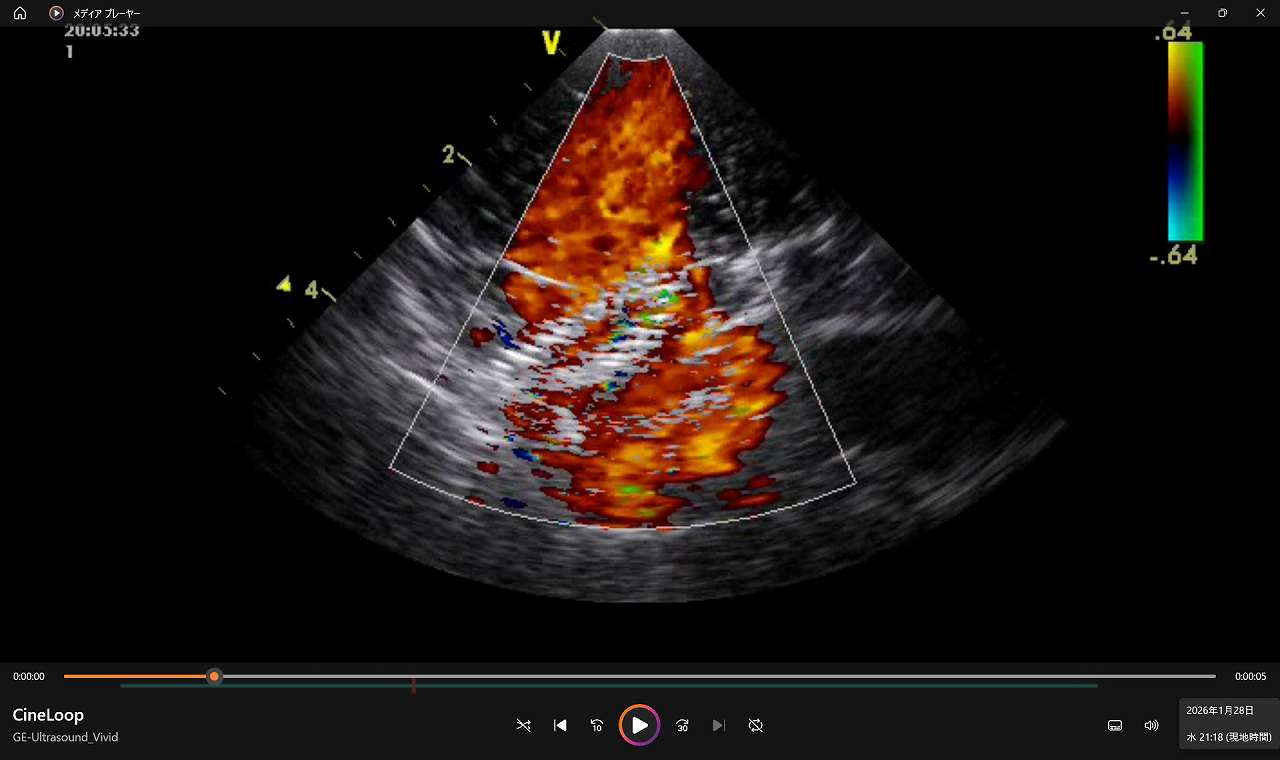

血流とデバイスの相互作用を視覚的に確認できること。

初代Lotus~LotusⅡへと進化する中で確立されたのは、大型モデルによって構造全体を俯瞰し、血流下でデバイス挙動を可視化できる環境です。